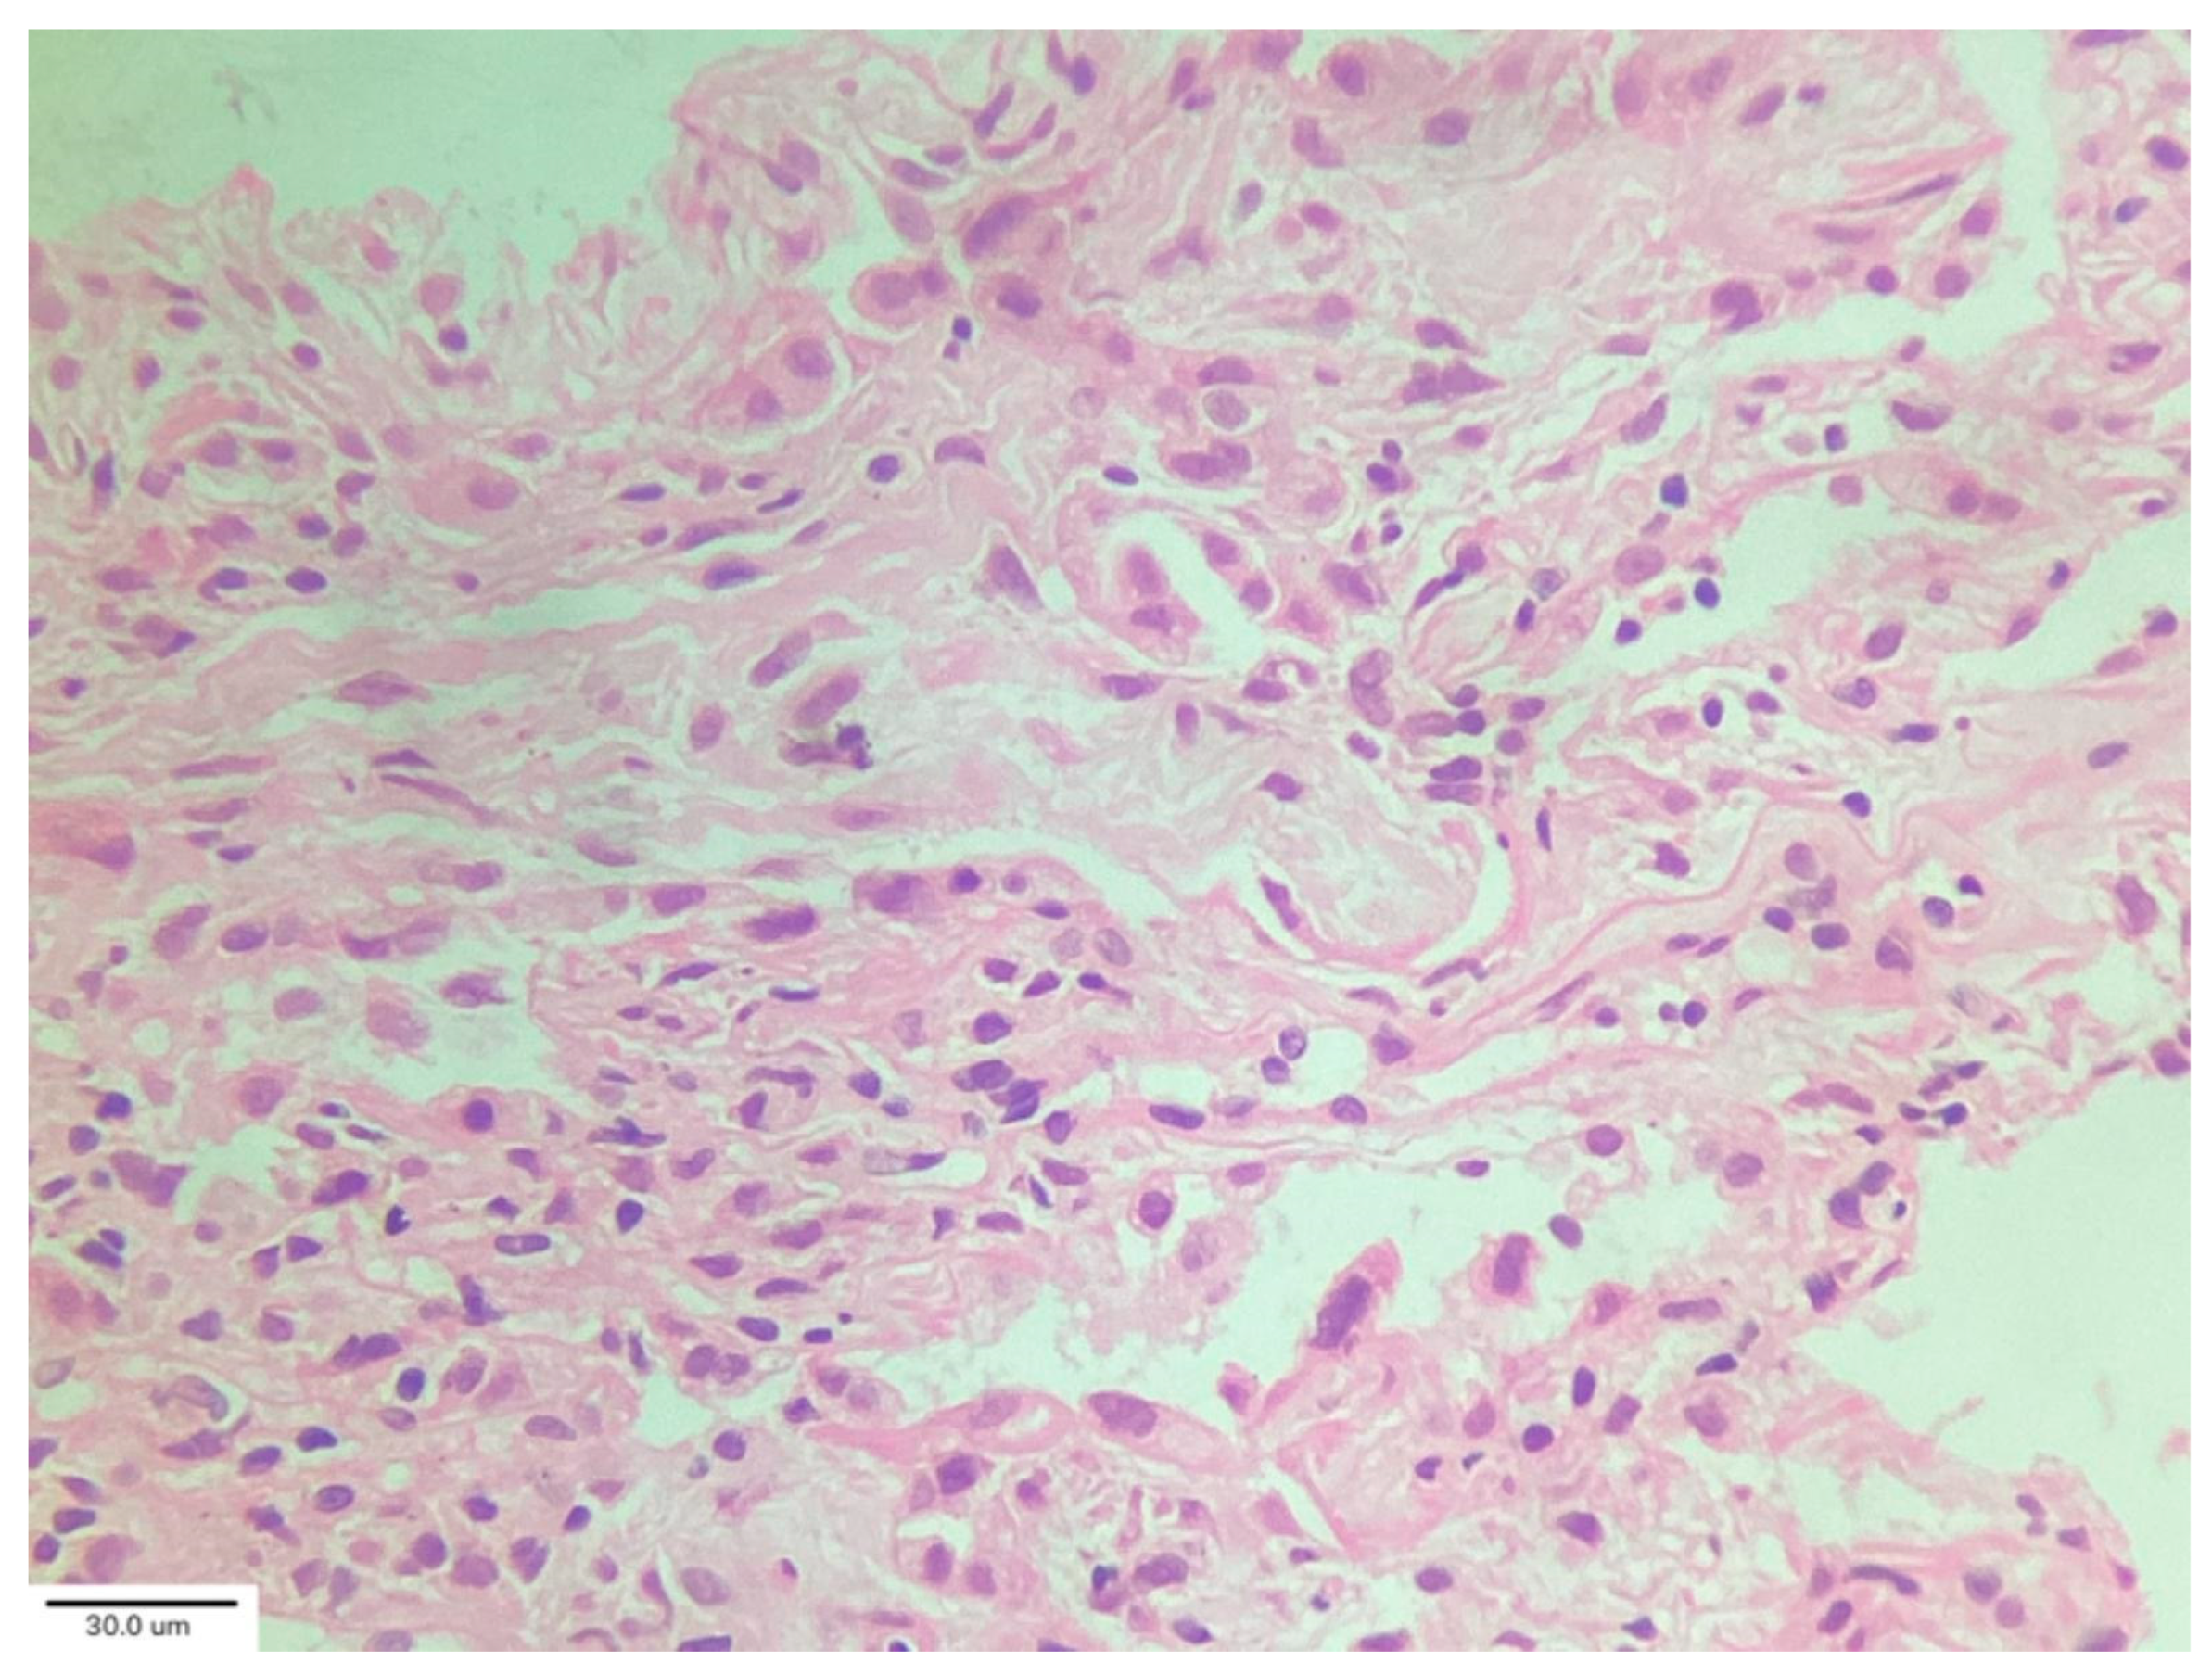

A case series by Aesif et al. [35] described the presence of diffuse interstitial fibrosis vaguely resembling an NSIP pattern (Figure 7) and areas of microscopic honeycombing in patients after a 4-month follow-up period. Fibroblastic foci were not observed in the biopsies. Incorporating biopsy findings into the post-COVID-19 multidisciplinary evaluation can help to identify key patient subgroups, understand the pathogenic mechanisms of ILD progression, and create better patient-specific treatment protocols that improve clinical outcomes. [36,37]

TBLC procedure is reported in Figure 8.

Figure 7. Diffuse interstitial fibrosis with nonspecific interstitial pneumonia pattern. Magnification: H&E ×100.

Figure 8. Endobronchial cryobiopsy procedure (A) supported by radiological imaging (B) of the right inferior lobe. Courtesy of Pallav L. Shah.